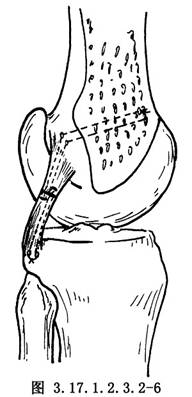

應用Bunnell縫合法,縫合鋼絲分別從股骨內髁與脛骨上端後側穿出固定(圖3.17.1.2.3.2-6)。